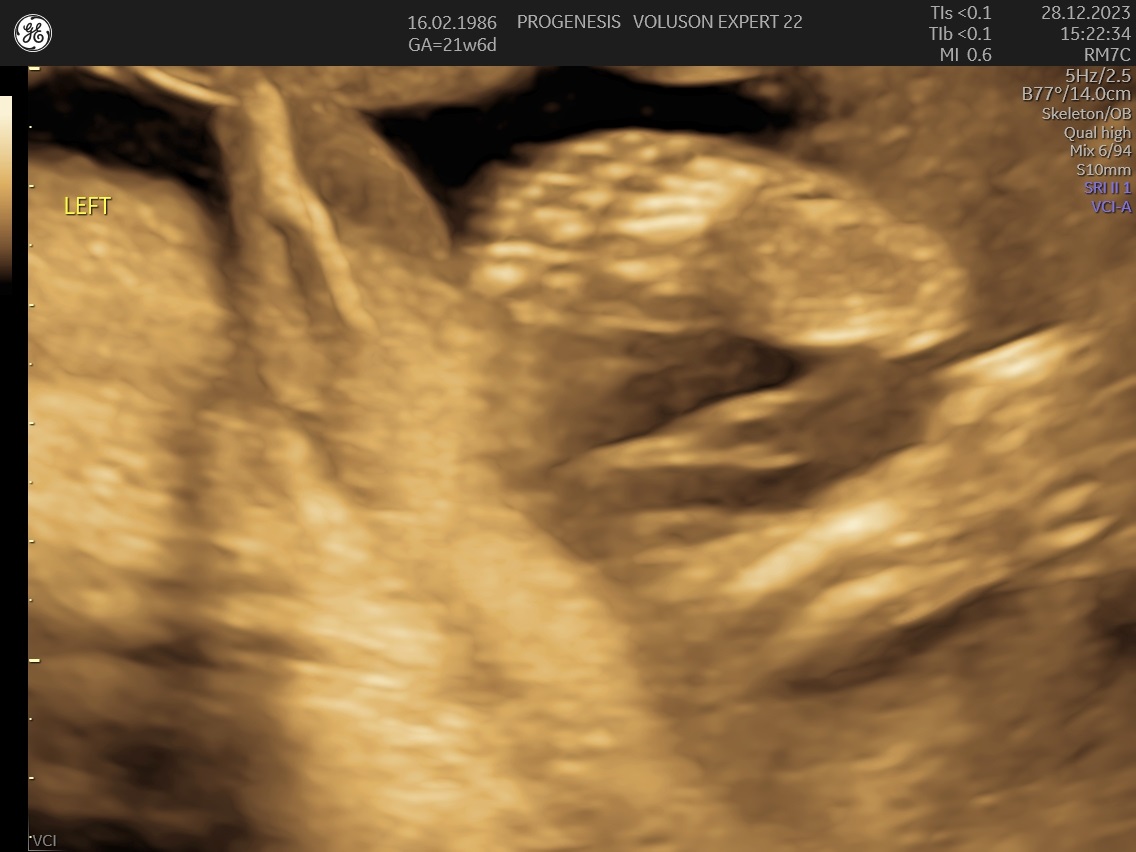

α) Η λεπτομερής αξιολόγηση της εμβρυϊκής ανατομίας, όπου αναγνωρίζονται τυχόν ανατομικές ανωμαλίες.

γ) Ο έλεγχος της ανάπτυξης του εμβρύου, του πλακούντα, του ομφαλίου λώρου και του αμνιακού υγρού.